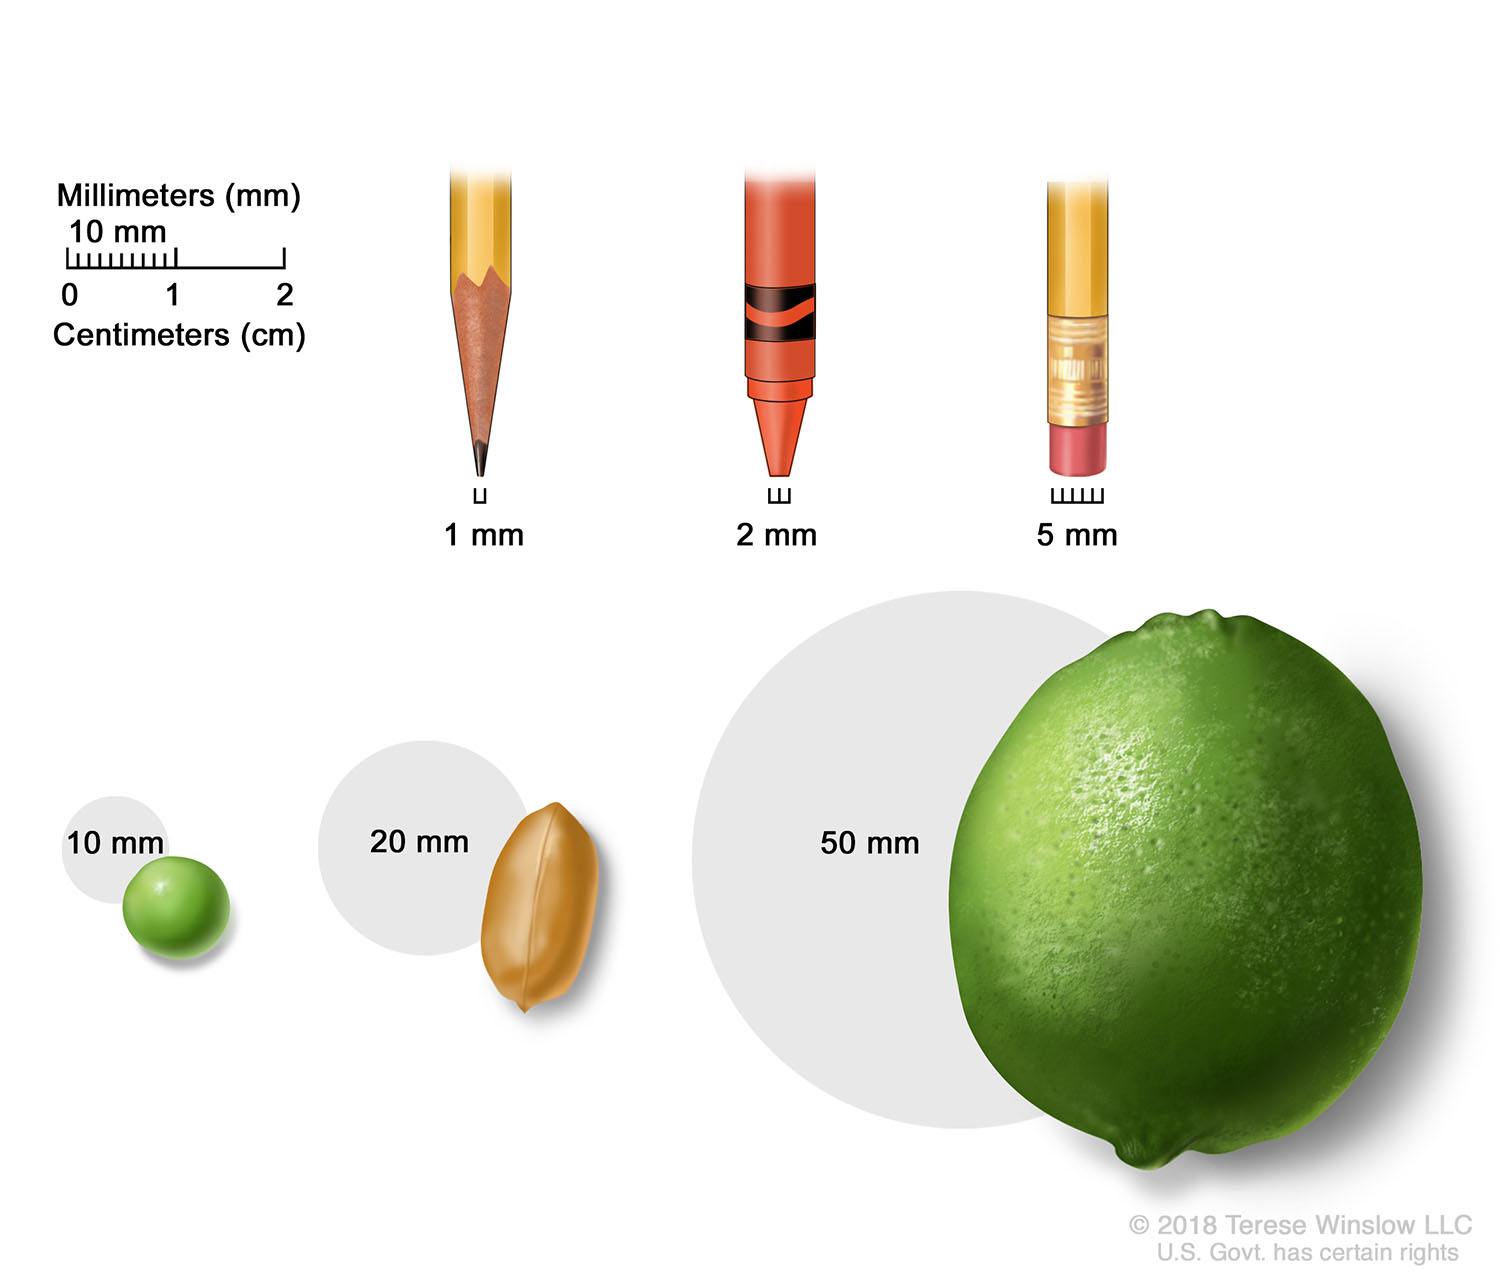

Breast Terese Winslow LLC Medical And Scientific Illustration

https://images.squarespace-cdn.com/content/v1/59b97dbfd2b857017400e500/1562174850181-Z72LG7JY6VPF2MZSD67A/tumor-sizes-millimeters-centimeters.jpg?format=1500w